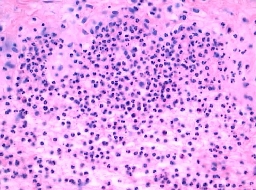

北京京城皮肤医院指出,刺激性接触皮炎无个体选择性,且无潜伏期,人接触均可立即引起皮肤急性炎症;变态反应(过敏反应),此型主要是迟发性变态反应(第vI型变态反应)。过敏反应是接触性皮炎中较常见者,被我们称为过敏性皮炎。